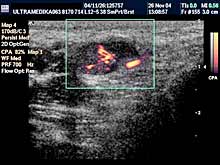

- 3D CPA - multiplanarna procena građe krvnih sudova tumora - radi

procene dobroćudnosti ili zloćudnosti opisane promene.

- 3D CPA je multiplanarna analiza kodiranih krvnih sudova organa male

karlice, ili novofomiranih tkiva-tumora, radi preciznije i tačnije

dijagnoze. Procena krvnih sudova grlića - ovom tehnikom - je obavezni

deo pregleda organa male karlice.